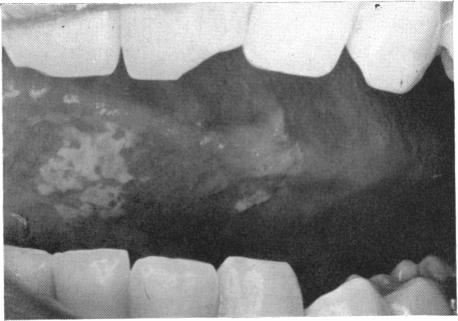

COOKE B E

Ann R Coll Surg Engl. 1964 Jun;34(6):370-83.